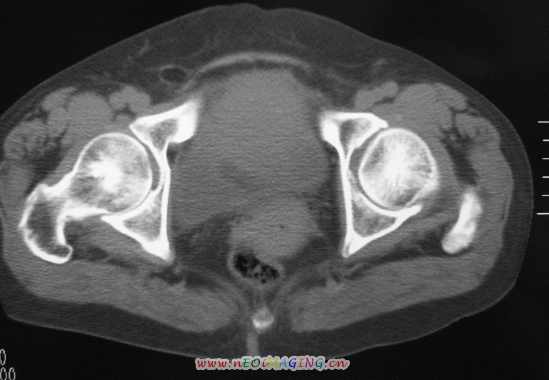

标题: CT11527:女56岁以右输尿管结石入院

女56岁以右输尿管结石入院

支持卵巢囊腺瘤;右侧输尿管第二狭窄处结石伴梗阻。

1)盆腔占位性病变,考虑来源于卵巢,囊腺瘤可能性大。2)右侧输尿管第二狭窄处结石伴梗阻。

今天病人已经手术证实为右附件囊肿,右侧输尿管第二狭窄处结石伴梗阻!!!

[病理诊断] CT11527:右附件囊肿,右侧输尿管结石。